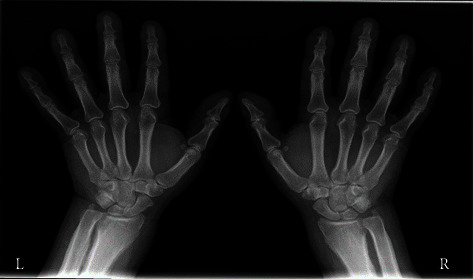

Abstract Image

Acromegaly and gigantism are hormonal disorders which develop as a consequence of chronic growth hormone hypersecretion. The prefix pseudo- is used to describe a certain clinical condition without a clearly proven characteristic of pathophysiological mechanism and basic biochemical features; pseudoacromegaly or acromegaloidism match the definition from above. In this case reports, we will try to provide a concise overview of diagnostic evaluation of acromegaloid physical appearance, while discussing two cases of patients who have similar clinical acromegaloid features as the first sign of the disease but have completely different etiologic backgrounds of their acromegalic appearance. The first case is of a 57-year-old male who presented with a marked acral growth and coarse facial features, but the diagnosis of secondary amyloidosis caused by multiple myeloma was confirmed just after biopsy of tongue and buccal mucosa. The second case is that of a 63-year-old male with an acromegaloid appearance caused by ectopic secretion of GH secreting lung carcinoma. The early diagnosis of ectopic acromegaly and pseudoacromegaly is still a challenging process. The key task is to confirm the GH axis abnormalities and establish the underlying disease, as a crucial step for faster treatment and need to avoid unnecessary therapeutic procedures to decreased mortality and improved quality of life.